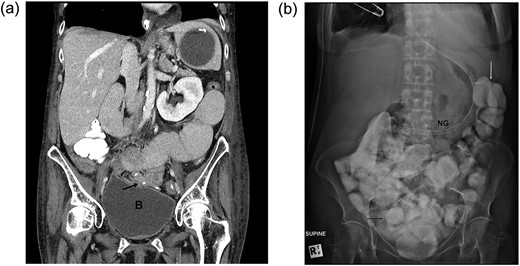

A 64-year-old Caucasian female underwent laparotomy for closed-loop small bowel obstruction secondary to adhesions from previous gynaecological surgery. Extensive division of adhesions was performed and small bowel resection was required for ischaemia. A side-to-side stapled entero-enterostomy was performed. Total parental nutrition was commenced due to a period of fasting prior to surgery and an expected protracted post-operative course. Prolonged ileus post-operatively, with abdominal distension and non-passage of flatus, continued to Day 9. CT scan showed non-passage of contrast at the anastomosis (Fig. 3a). Repeated enema and oral gastrograffin (Bayer, Germany) challenges failed. Dexamethasone 8 mg intravenously daily was instituted on Day 12 post-operatively. Bowel function returned spontaneously by Day 15 and repeat CT scan (Fig. 3b) with oral contrast showed complete resolution of the obstruction and proximal small bowel dilatation. Recovery occurred uneventfully.

(a) CT scan of the abdomen and pelvis in a patient who underwent adhesiolysis and small bowel resection. The scan shows hold of the contrast at the level of the anastomosis (black arrow) just over the dome of the bladder (B=bladder). (b) A plain film of the abdomen, following Dexamethasone challenge, confirms the presence of contrast in the distal ileum (black arrow) and the colon (white arrow).